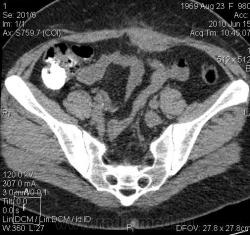

Женщина 40 лет, чуть больше месяца после операции по поводу гнойного сальпингита. Свищ передней брюшной стенки в области п/о рубца на 3 см влево от сагитальной линии, температура 38. СОЭ=35 мм/ч, палочкоядерные 16, лейкоциты 10.

При проведении фистулографии легко поместилось 20 мл урографина. На рентгенограмме контрастировалась слепая кишка. Взята на КТ. Заключение: сформировавшийся наружно-толстокишечный свищ, абсцесс передней брюшной стенки. Ваше мнение? Прошу помочь с классификацией, верна ли терминология?

Жаль на этих изображениях весь свищ до слепой кишки не прослеживается. А нет ли у него ответвления к органам м. таза? Абсцесс передней брюшной стенки – это утолщение мягких тканей по средней линии её?

"Веточек" в малый таз не нашла, хотя матка неоднородна, без увеличения. Да, веретенообразное утолщение мышц передней брюшной стенки, местами жидкостной плотности, с мелкими уровнями, тяжистость подкожно-жировой клетчатки по ходу свища. Свищ спадается, около 4 см в брюшной полости виден крайне плохо, и на сканах тоже.

Сначала была обычная фистулография. На КТ взяли после обнаружения контраста в слепой кишке на рентгенограмме, чтоб определиться с состоянием органов брюшной полости и таза. При проведении КТ дополнительно контраст не вводился - ни в свищ, ни болюсно.